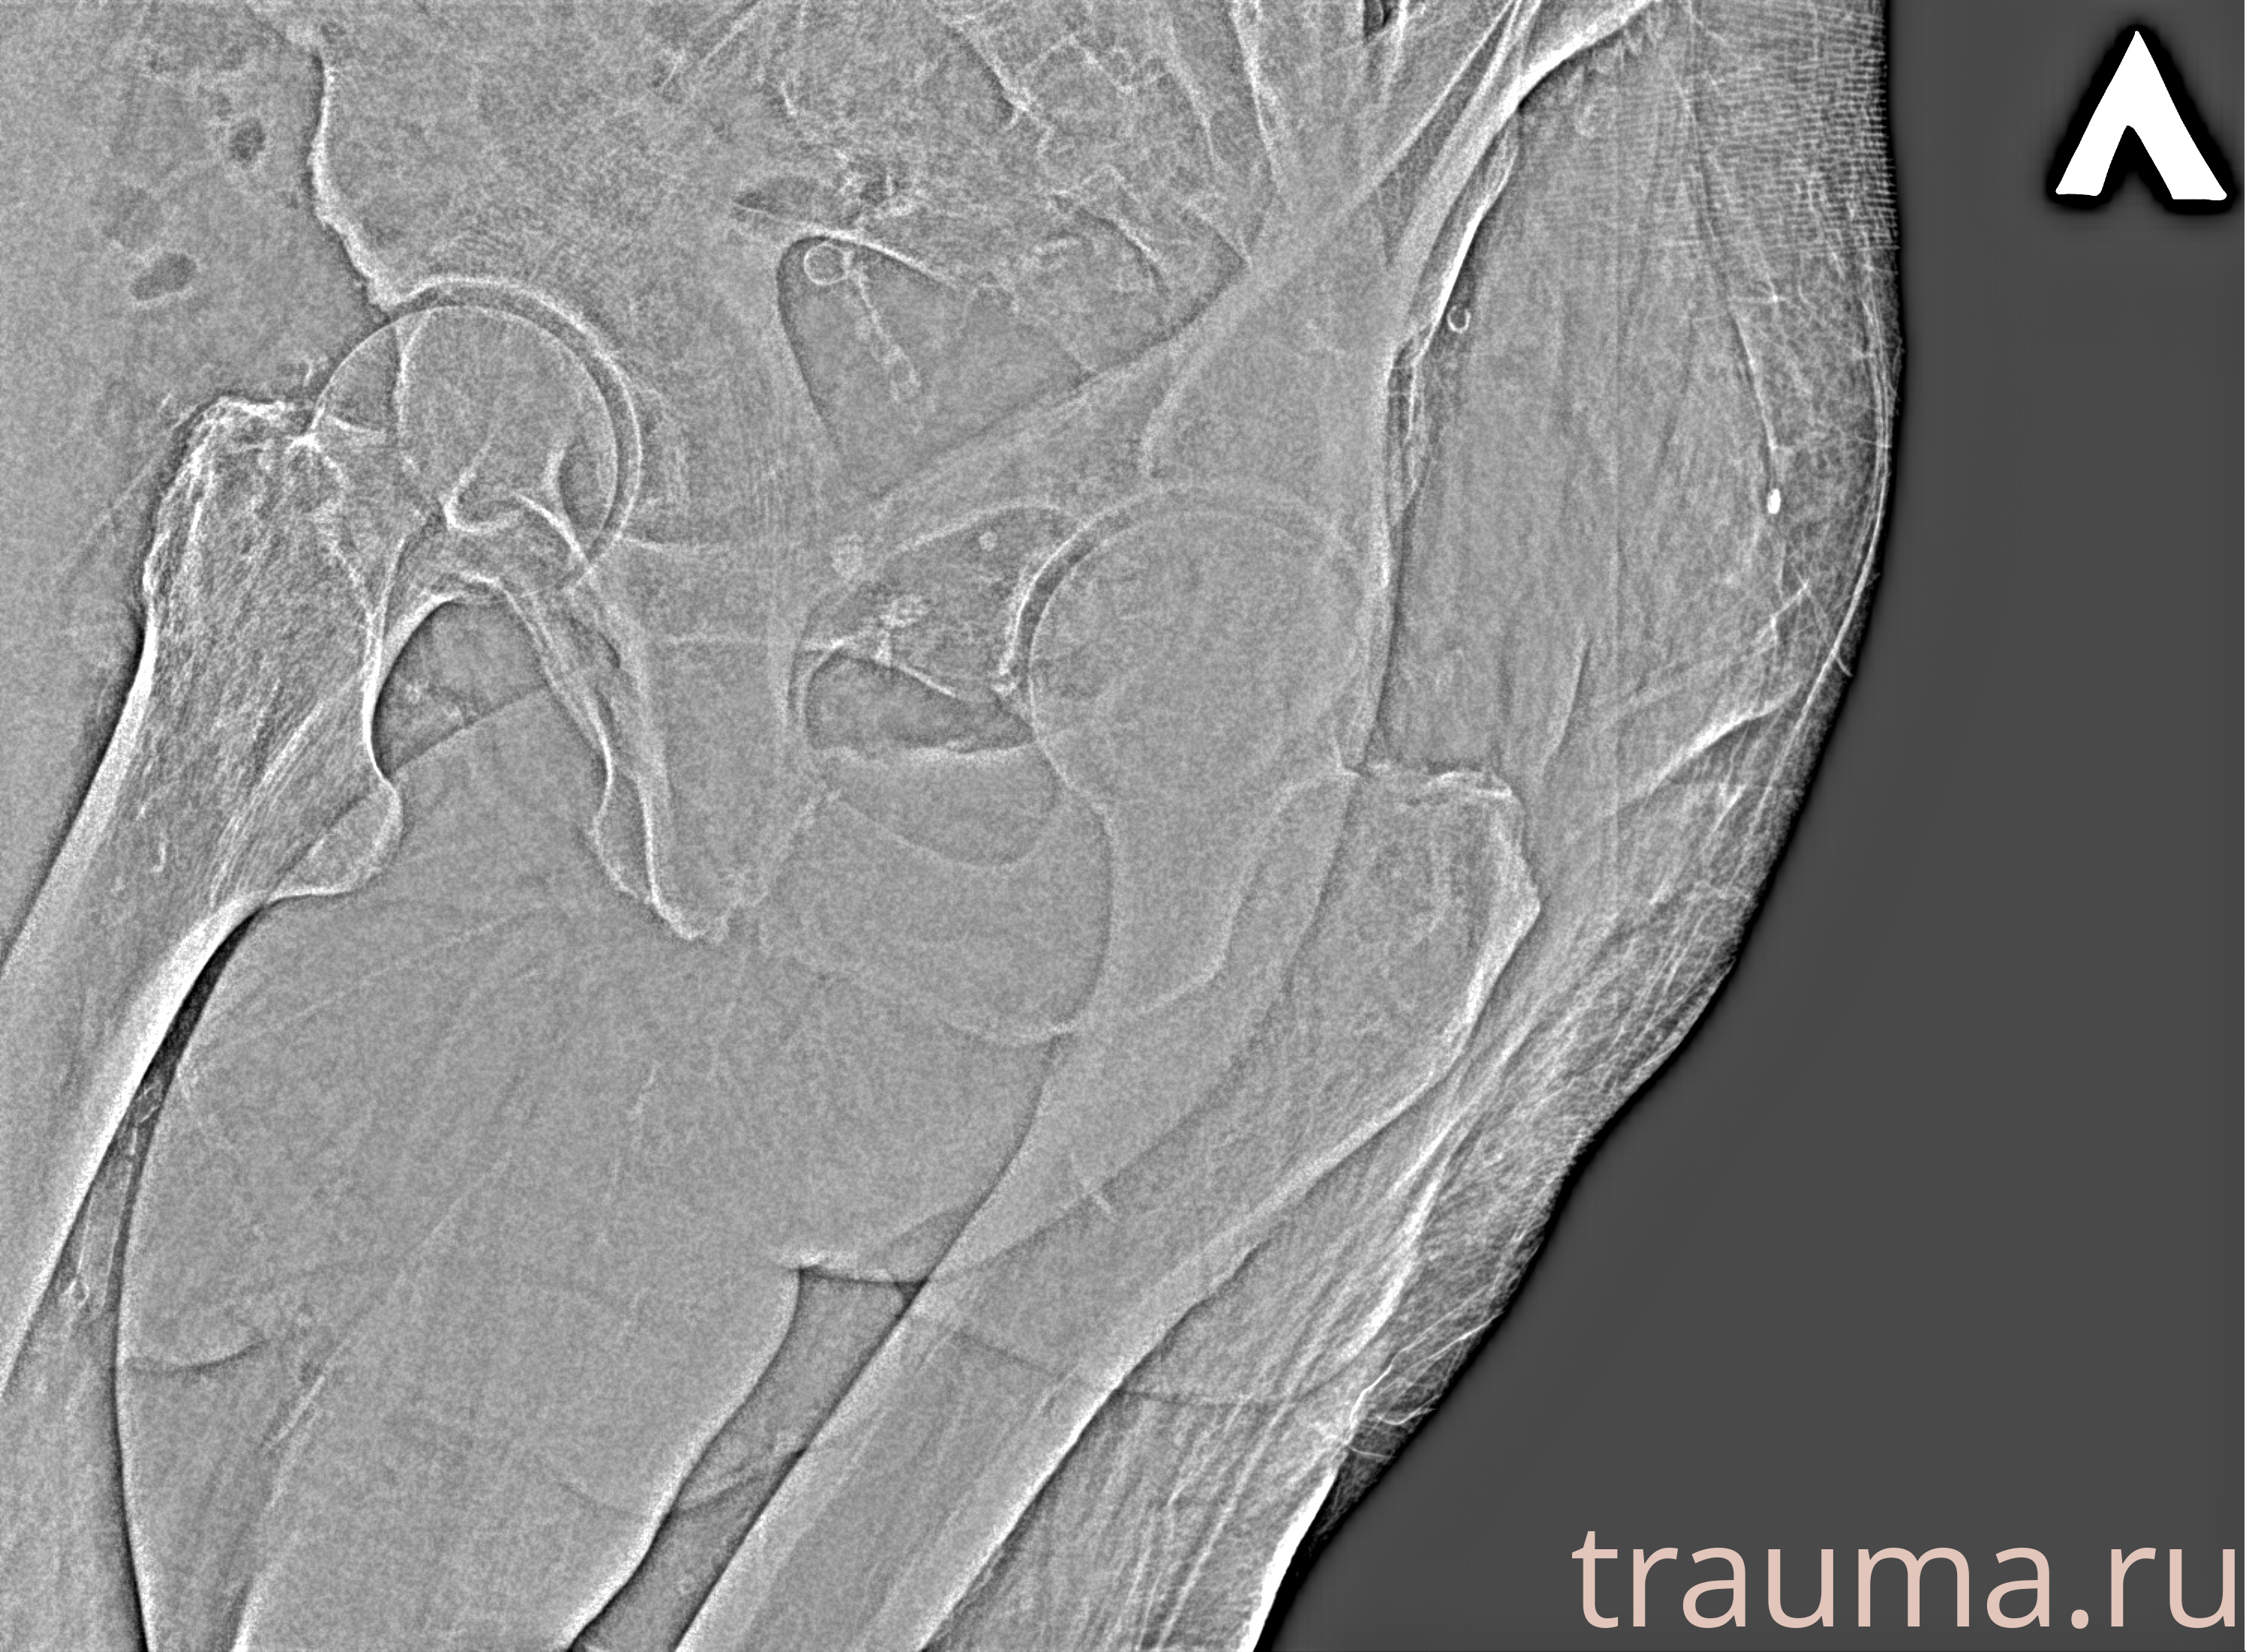

Рентген на дому: по вашему адресу приезжает врач-рентгенолог, травматолог-ортопед с мобильным рентгеновским аппаратом, проводит диагностику травмы или заболевания, делает необходимые рентгенограммы, дает рекомендации по дальнейшему лечению. Получить качественные снимки в домашних условиях возможно благодаря уникальной методике, разработанной МосРентген Центром для института  Склифосовского